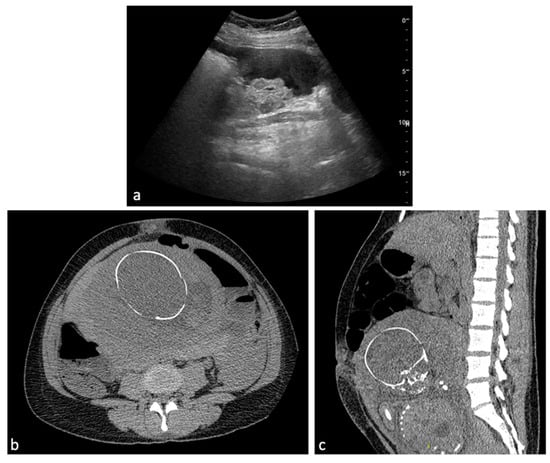

Placenta Accreta Spectrum (PAS) disorders encompass a spectrum of pathological conditions characterized by abnormal placentation, leading to potential complications, from vaginal bleeding to massive obstetrical hemorrhage [14,16]. These disorders, which include placenta accreta, increta, and percreta, arise when the placental villi invade and adhere to the myometrium beyond the normal depth, often reaching the uterine serosa or adjacent organs [79]. US is the first-line technique for the evaluation of the placenta. However, when US findings are equivocal, MRI is the second-line diagnostic tool to evaluate PAS disorders. Dark intraplacental bands on T2WI, increased placental thickness, placental/uterine bulge, myometrial thinning, bladder wall interruption, focal exophytic mass, and abnormal vascularization of the placental bed are the main MRI findings suggestive of a PAS disorder [80,81,82] (Figure 9). Antenatal recognition of PAS disorders is crucial for optimizing management strategies, which may include planned cesarean delivery, preoperative endovascular interventions, and coordination with a multidisciplinary team to mitigate the risk of severe bleeding and associated maternal morbidity [57,83].

Figure 9.

Placenta percreta. A 38-year-old woman at 27 weeks of gestation with placenta previa percreta. Sagittal (a) and axial (b) T2W SSFSE images show a heterogeneous placental signal with some low signal intensity bands representing venous lakes (arrows). There is also a focal uterine bulge with thinning of the overlying myometrium. The patient underwent a caesarean section and extraction of the fetus but no secondment due to placenta percreta. In the post-partum MRI (c), signs of placental percreta were still present with an image of bladder infiltration (arrow), later confirmed at cystoscopy. It was decided to perform endovascular devascularization of the placenta percreta left in situ before proceeding to hysterectomy. Preliminary arteriography of the abdominal aorta documented hypertrophy of both uterine arteries, clearly greater on the right, which exuberantly vascularized the hypertrophied placenta, supplying multiple intraplacental high-flow vascular lakes (d). After superselective catheterization with a coaxial microcatheter of both uterine arteries and some of their distal branches, bilateral embolization was performed by infusion of a suspension of embolizing particles. The procedure was completed with release of 3 platinum microspirals (3 mm diameter) at the level of the distal right uterine artery (e), proximal to the origin of the main collaterals and 2 microspirals (3 mm) at the origin of the left uterine artery. At the end of the operation, satisfactory uterine and placental devascularization was shown (f).